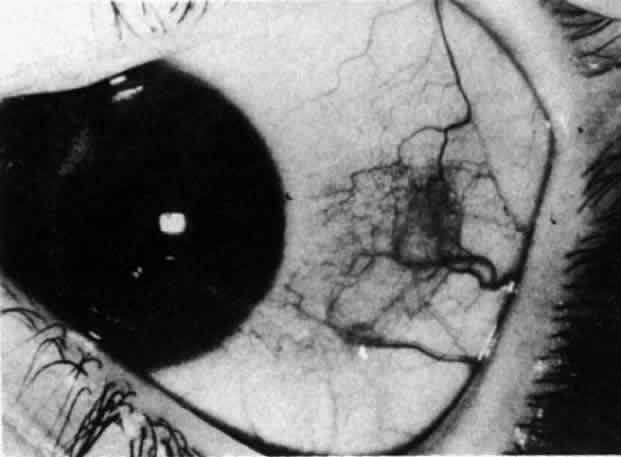

Fig. 31. Diffuse anterior scleritis after treatment. The dilated abnormal blood

vessels remain even though no inflammation remains. Fig. 31. Diffuse anterior scleritis after treatment. The dilated abnormal blood

vessels remain even though no inflammation remains.

|

In this relatively benign form of scleral inflammation, the fluorescein

angiogram reveals a rapid flow pattern in which the transit time of the

dye is very rapid (as in episcleritis) (Figs. 32 and 33). Subtle changes occur in the capillary network, and abnormal leaking

vessels appear after prolonged inflammation. These changes do not disappear

after the inflammation subsides or is treated (see Fig. 31).  Fig. 32. Diffuse anterior scleritis associated with corneal edema. The limbal vessels